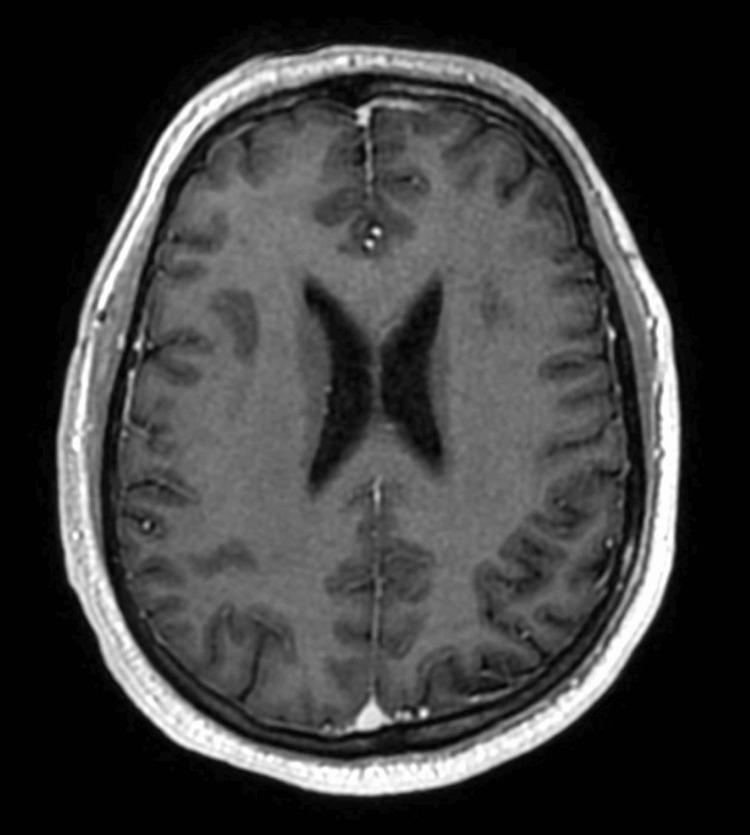

一例非小细胞肺癌所致MRI阴性的柔脑膜疾病病例

A Case of MRI-Negative Leptomeningeal Disease From Non-small Cell Lung Cancer.

Leptomeningeal disease (LMD) is a rare complication of advanced non-small cell lung cancer (NSCLC), associated with a poor prognosis. We report the case of a 55-year-old man, who presented with a metastatic NSCLC with limited brain and abdominal metastases. He was treated with both chemoimmunotherapy and stereotactic radiotherapy (SRT) to the brain. Despite treatment, the patient experienced progressive neurological symptoms not in keeping with the extent of disease seen on imaging of the brain. Due to this incongruence between symptoms and radiologic findings, he underwent a lumbar puncture, which had positive cytology for LMD. He had a rapid progression of symptoms and died six days after the discovery of LMD. We review the available literature regarding the prevalence of MRI-negative LMD from a solid primary malignancy.

摘要

软脑膜疾病(LMD)是晚期非小细胞肺癌(NSCLC)的一种罕见并发症,预后较差。我们报告了一例55岁男性病例,该患者患有转移性NSCLC,脑和腹部转移灶有限。他接受了化疗免疫治疗和脑部立体定向放射治疗(SRT)。尽管进行了治疗,但患者仍出现了与脑部影像学所见疾病范围不符的进行性神经症状。由于症状与放射学检查结果不一致,他接受了腰椎穿刺,脑脊液细胞学检查显示LMD呈阳性。他的症状迅速进展,在发现LMD后六天死亡。我们回顾了有关实体原发性恶性肿瘤中MRI阴性LMD患病率的现有文献。